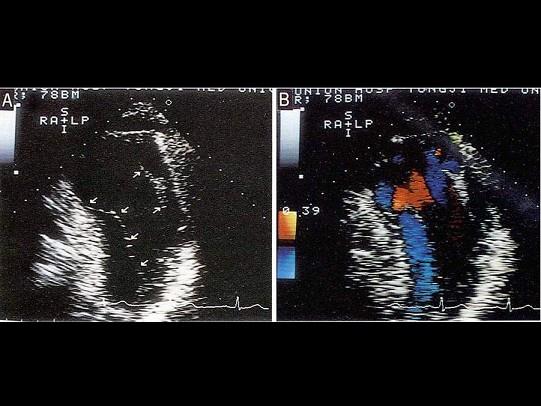

问题 该病例最可能的诊断?(?)

选项 A.主动脉增宽 B.主动脉壁内膜增厚 C.夹层动脉瘤 D.假性动脉瘤 E.真性动脉瘤

答案 C